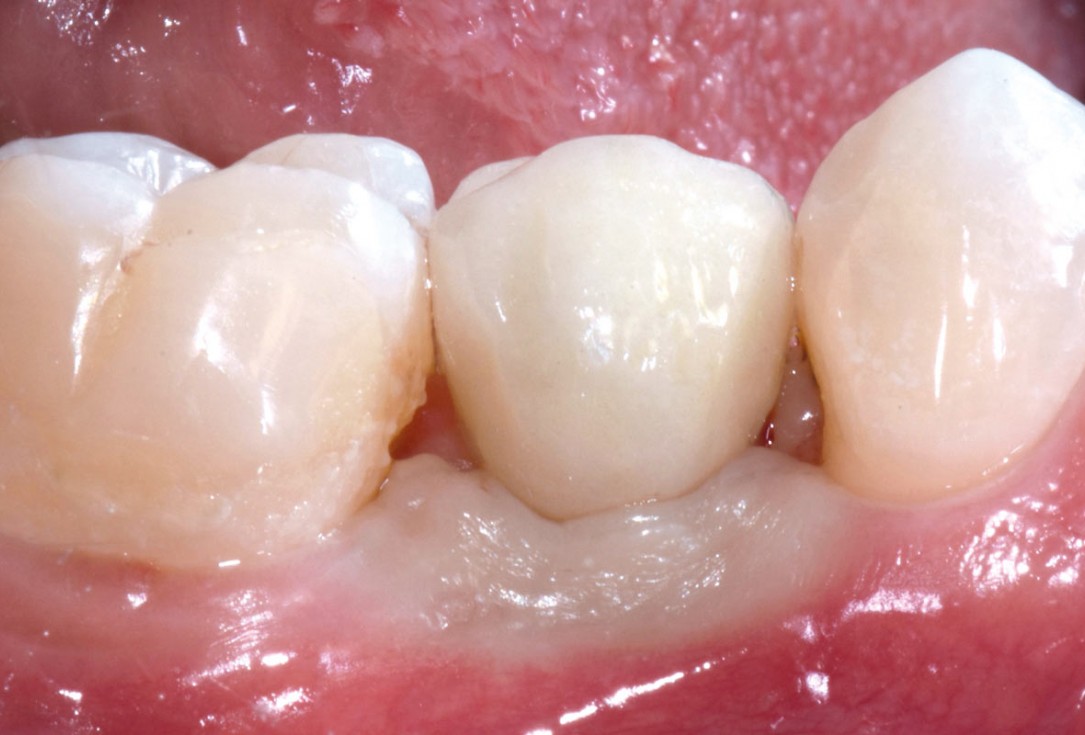

15/17 - Provisional crown placed to shape the soft tissueApplication of mucoderm® for soft tissue management around single implants at second stage surgery Dr. C. De Annuntiis

16/17 - Follow up at 2 years presenting stable soft tissues with final restorationApplication of mucoderm® for soft tissue management around single implants at second stage surgery Dr. C. De Annuntiis